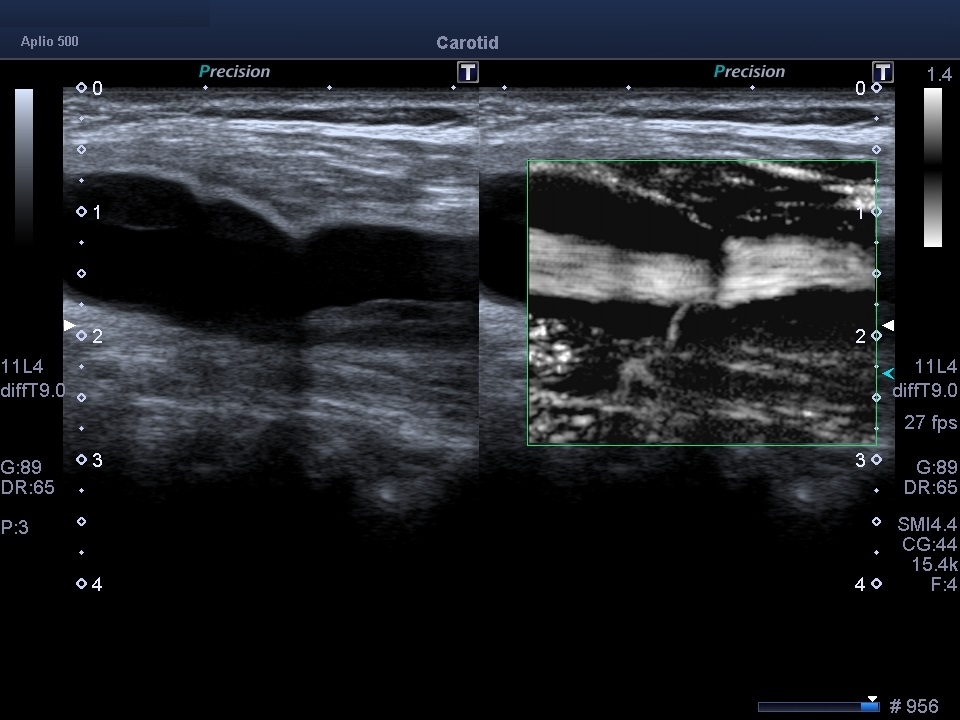

Неінвазивна неоваскуляриція каротидних бляшок з SMI

Значна частка ішемічних інсультів спричинена емболонебезпечними (нестабільними) бляшками сонної артерії з неоваскуляризацією всередині бляшок як ключовою ознакою її нестабільності. Неоваскуляризація не виявляється за допомогою звичайного доплерівського картування. Для проведення такої діагностики може використовуватися ультразвук з контрастом (CEUS, але його використання обмежене в клінічній практиці, оскільки вимагає внутрішньовенної ін’єкції контрасту. Особливу роль відіграє унікальна, неінвазивна, доплерівська мікросудинна візуалізація (SMI) без контрасту, що використовує алгоритм для усунення шумів та рухів стінок, зберігаючи при цьому низькошвидкісні сигнали кровотоку, що дозволяє оцінити ступінь неоваскуляризації бляшок. SMI є перспективною неінвазивною альтернативою CEUS для оцінки стабільності каротидних бляшок.